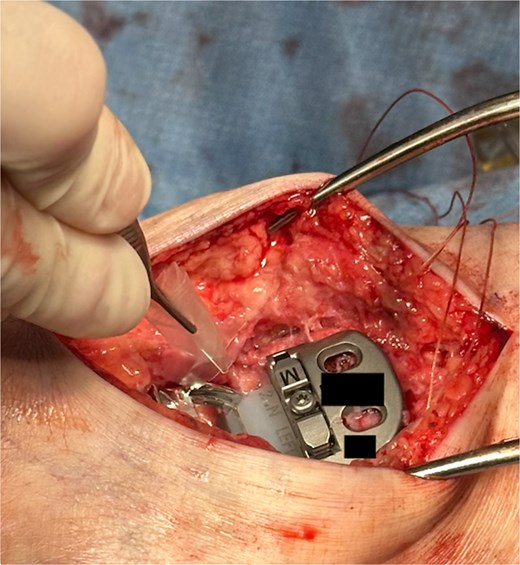

The hydrogel sheet is composed of a biocompatible, bioresorbable HA alginate. The sheet is placed within the posterior ankle capsule after tibial and talar components have been implanted, but before final polyethylene insertion (Fig. 1). The aqueous citrate wetting solution is then added to the hydrogel sheet surface to activate. The goal of this application is to prevent return of scar tissue formation in the posterior ankle after the previous capsule release performed earlier in the surgery. Once all implants and poly have been finalized and just before closure, additional VersaWrap is placed in the medial and lateral ankle gutters to decrease risk of scar tissue and ectopic bone formation (Fig. 2).

VersaWrap placed in the posterior ankle following capsular release.